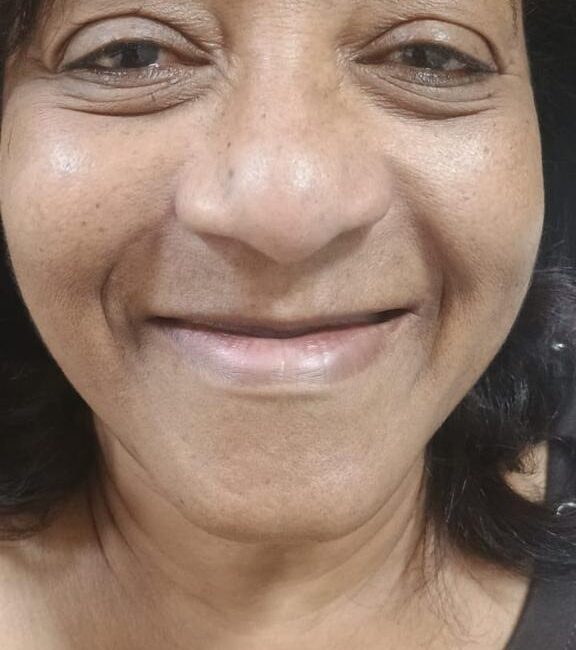

– Proporciona ao paciente a funcionalidade dental quase instantaneamente, melhorando a estética e a confiança.

– Reabilitação Rápida: Permite a colocação de próteses fixas em um único procedimento cirúrgico.

– Estética Imediata: Os pacientes podem sair da clínica com um sorriso restaurado no mesmo dia.